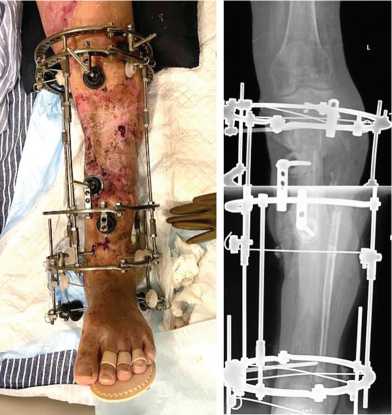

На 261-е сутки после ранения (182-е сутки после остеотомии) отметили контакт фрагмента и проксимального отломка через зону инвагинации (рис. 3). В целях обеспечения контакта проксимального отломка и перемещаемого фрагмента дистального отломка на 262-е сутки после ранения (183-и сутки после остеотомии) выполнили резекции зоны инвагинации и костно-хрящевого комплекса на торце проксимального отломка и перемещаемого фрагмента, открытую репозицию отломков, перемонтаж аппарата Илизарова. Достигнут контакт торцевых частей проксимального отломка и перемещаемого фрагмента (рис. 4). В последующем проводили компрессию между проксимальным отломком и фрагментом, «воспитание регенерата» методом «аккордеона».

Рис. 3. Фото и рентгенограмма левой голени при сближении проксимального отломка и перемещаемого фрагмента (инвагинация)

Рис. 4. Рентгенограмма левой голени после операции устранения инвагинации, резекции зоны ложного сустава, репозиции отломков, перемонтажа аппарата Илизарова